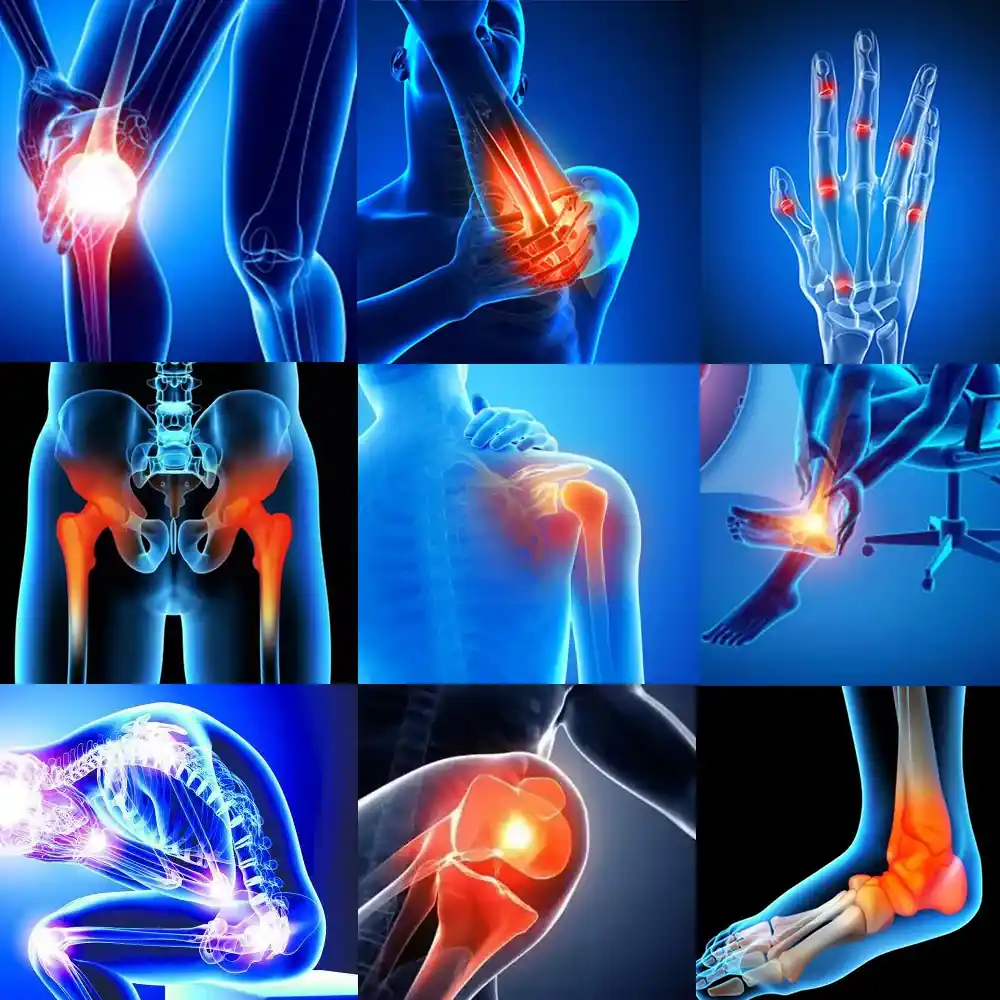

There are also systemic layers. People with secondary osteoarthritis (caused by another condition like psoriatic arthritis, ankylosing spondylitis, or juvenile idiopathic arthritis) may have heightened immune sensitivity. Their bodies may release inflammatory markers even in mild stress situations.

II. 10 Common Causes of Osteoarthritis Flare-Ups (and How to Manage Each One)

Sometimes, osteoarthritis flares feel random. You wake up, and your degenerative joint disease just… decides it’s mad today. But usually, there’s a reason — or ten of them. Recognizing your personal triggers helps you shorten recovery time and even prevent future flares.

7. Hormonal Fluctuations (especially in women)

- Cause: Changes in estrogen can heighten joint inflammation.

- Fix: Track symptom timing. Ensure balanced nutrition and consider consulting a Summit provider or endocrinologist if cycles strongly affect flares.

Estrogen helps protect joint cartilage, so when levels drop — like during perimenopause — inflammation can creep up. It’s subtle but noticeable.

Adding more anti-inflammatory foods and staying consistent with gentle exercise can balance hormones and support OA flare duration reduction.